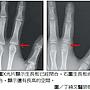

※ 引述《omare (金州勇士王)》之銘言: : 大家好 太嘎好 : 25歲還有辦法長高嗎 : 如果不輪班 每天打籃球 跳高高 還有機會嗎 : 要怎麼知道自己還有沒有機會呀 : 去找骨科嗎? : 禁慾有差嗎 : 我如果不要國二就開始打手槍是不是能在高5公分阿 : 幹 170真的很矮啦 想要172比較剛好 : QQ : 還是基因阿 我雙親 157 168 只能找專科醫院把腿骨鋸開再生長 除此之外沒有別的方法了 鋸下去要嘛認命吧! 170男生真的是矮 而且你應該是基因的問題影響最大 基因佔身高50%的影響 基本上一輩子不要想在歐兔徵女了 -- ※ 發信站: 批踢踢實業坊(ptt.cc), 來自: 60.245.65.132 ※ 文章網址: https://www.ptt.cc/bbs/Gossiping/M.1461900190.A.C85.html